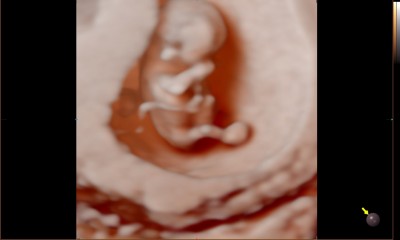

Kızlar 11 haftalığım doktorum dalında gerçekten iyi bir doktor cinsiyet tahmininde bulundu ama sizinde gördüğünüzü tahminlerinizi merak ediyorum:)

Herkes erkek tahmin etmiş ;) Doktorum %1 yanırım dedi Kız müjdesi verdi bir oğlum var Rabbim ayıpsız kusursuz sağlıklısını versin ama iki meyvedende olsun istiyor insan :)